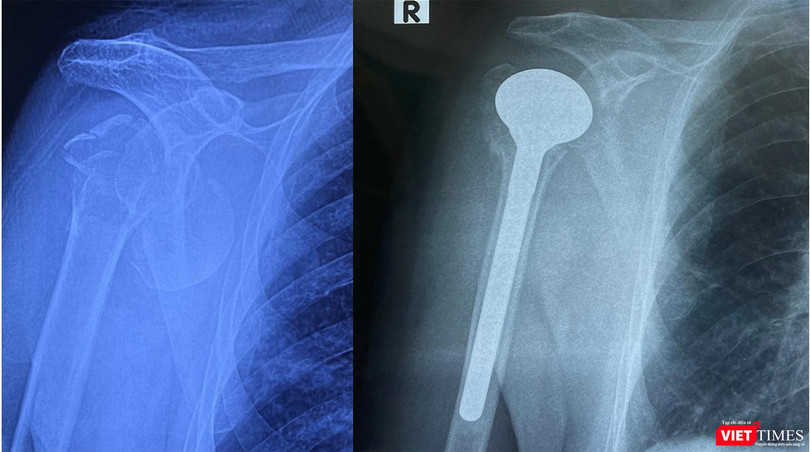

Tại Bệnh viện Hữu nghị Việt Đức, bệnh nhân đã được các bác sĩ Khoa Phẫu thuật Chi trên và Y học thể thao thăm khám và chẩn đoán bị gãy cổ xương cánh tay làm nhiều mảnh kèm theo trật khớp nên không thể đưa đinh nẹp vào kết hợp xương.

Sau khi hội chẩn liên chuyên khoa Tim mạch, Gây mê hồi sức, Chấn thương chỉnh hình, ThS.BS Lưu Danh Huy - Phó Trưởng khoa Phẫu thuật Chi trên và Y học thể thao – Bệnh viện Hữu nghị Việt Đức - đã quyết định thay khớp vai bán phần cho người bệnh.

ThS.BS Lưu Danh Huy cho biết, đây là ca bệnh hy hữu, bệnh nhân là người cao tuổi nhất Việt Nam được thay khớp vai bán phần. Ở bệnh nhân cao tuổi với những bệnh lý nền như đái tháo đường, cao huyết áp, bệnh lý mạch vành sẽ rất nhiều nguy cơ tai biến trong phẫu thuật. Bên cạnh đó, đối với những bệnh nhân cao tuổi xương loãng thì nguy cơ gãy xương khi đưa dụng cụ phẫu thuật vào rất cao, cũng như có sốc phản vệ đối với xi măng gắn dụng cụ vào xương, tử vong ngay trên bàn mổ.